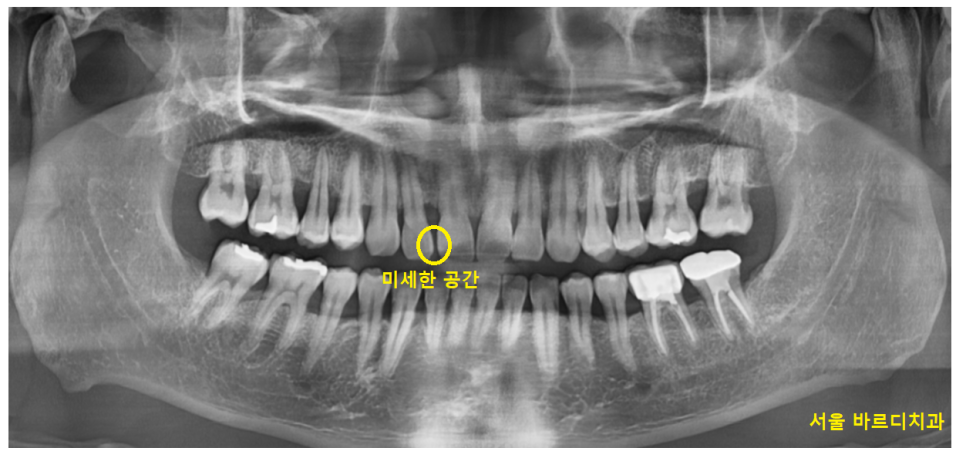

23.01.30

고덕 그라시움 치과 방문해주신 환자분의 경우에도

미세하지만 앞니 사이 공간이 있었습니다.

▼집중!▼

작은 틈새이지만

공간이 있어서 떼우고 싶다고 하셨습니다.

아무래도 반대편 치아의 경우

붙어있어서 더 비교가 되셨나봐요~

반대편 치아만 해도 잘 붙어있는데

유독 윗니 앞 부분 치아만 틈이 있네요~

오늘 환자분의 경우

옆 치아와의 공간이 1mm도 채 안되어서

(아주 작은 공간이라는 뜻입니다!)

벌어진 앞니 메꾸기 레진으로 가능했습니다~!